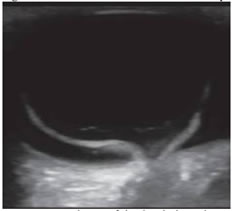

INTRODUCTION The retina, as we know, is a layer of organized neurons which line the posterior portion of the posterior chamber of the eye. The retina consisting of photoreceptors, neurons and support cells, is lined anteriorly by the vitreous and posteriorly by the choroid, and has a central portion called the macula. The macula has a high concentration of photoreceptors and is responsible for capturing central vision. More precisely there is a 1.5 mm central portion in it with the highest concentration of photoreceptors called the fovea, which forms the basis of classification of Mac- On and Mac- Off retinal detachment. Normal anatomical landmarks of the eye as visualized on ultrasonographic imaging are depicted in Figure 1. Figure 1: Normal anatomical landmarks of the eye on ultrasonographic imaging RD (Retinal Detachment) occurs when this layer separates from the underlying epithelium, resulting in ischemia and leading to progressive photoreceptor degeneration which might result in complete blindness of the affected eye if not properly treated or even with delayed treatment and surgeries performed beyond the stipulated time period1, 2 Depending on the type of retinal detachment, the time interval of the surgical treatment is the key to preservation of vision.3 Retinal detachments as described are of three types4: Rhegmatogenous RD (RRD), Tractional RD (TRD) and Exudative and Serous RD. RRD is the most common, and is caused by a tear in the retina (‘Rhegma’ meaning ‘tear’) with consequent extension of vitreous into the potential space below the retina and separation of retina from choroid, requiring surgery. TRD is caused due to pre-retinal membrane formation and scarring which pulls away the retina from its attachment. It is seen in diabetes, trauma, Eales disease and sickle cell retinopathy also indicating surgery. Exudative and Serous RD is less common and along with TRD will not be referred in this study. Rhegmatogenous Retinal Detachment (RRD) can be of two types: Mac- Off and Mac- On RRD. Mac- Off (Macular- Off) rhegmatogenous retinal detachments occur when the retinal detachment also involves the macula and extends to the fovea. Mac- On (Macular- On) retinal detachments on the other hand spare the macula and do not extend to the fovea.4 (Figure 2) a b Figure 2: Ultra-sonographic images of a) Mac- On and b) Mac- Off Retinal Detachments Ultrasound has been evolving in the background of vast advancements in MRI and CT scans in the field of Radiodiagnosis and has proved to be an effective, safe and cost effective radiological investigation giving enormous information in minimum time. However radiologists mostly tend to limit themselves to abdominal or fet al. ultrasound leaving small part ultrasounds mostly to the experts. An area not so commonly explored is ultrasounds or B scans of the eye. It has been found that visualization of the eye is equally possible with a routine ultrasound machine even without the availability of a B scan. Orbital ultrasounds are regularly referred to the Department of Radiology for various pathologies including screening to rule out retinal detachment, particularly prior to cataract surgeries or following trauma or infections of the eye. Radiologists predominantly suffice themselves by reporting the absence or presence of retinal detachment. No classification of the type of retinal detachment is investigated beyond this finding, in majority of the cases. Mac- Off and Mac- On, as described above are classifications of retinal detachment which are less known and very rarely reported by the radiologists, and yet are findings which hold urgent importance in the final outcome of the patients’ vision being restored. Differentiating these two types of retinal detachment give crucial evidence for the outcome of the treatment planned by the ophthalmologist besides giving critical time frame for performing any surgery planned on the affected eye. Overlooking this simple data and a lack of reporting and understanding of the value of this finding may lead to an erroneous miscalculation of the time of surgery and a delay in the surgery, based on this data provided by the radiologist, leading to total permanent blindness. Not only does this radiological finding gives crucial data allowing prompt surgery and saving of the vision, but also provides any unnecessary medico legal repercussions. Retinal detachment on ultrasounds appears as an echogenic linear floating membrane which is attached to the optic disc, differentiating it from PVD (posterior vitreous detachment) where the optic disc is free of the attachment of the membrane.4, 5 (Figure 3) Mac- Off RD can be visualized on ultrasounds as retinal detachment with retina lifted away from the fovea, whereas in Mac- On RD, the retina is attached at the fovea sparing the macula. Mac– Off and Mac– On classification of RD are relatively less known entities and rarely reported or evaluated. Findings of Mac- On RD on urgent sonographic evaluation become critical, requiring urgent surgical repair to prevent total blindness.

RESULTS A total of 50 ultrasounds of the eyes were studied for retinal detachments. Out of the 50 cases studied, 41 were identified or diagnosed as Mac- Off retinal detachment and 9 were diagnosed as Mac- On retinal detachment. The findings on ultrasound revealed a linear echogenic membrane floating in the vitreous which was attached posteriorly at the disc producing a V shaped structure unlike the finding in PVD (Posterior Vitreous Detachment) where the membrane was not attached along the posterior margin. (Figure 4) The initial differentiation on ultrasound was between RD and PVD where posterior attachment and a V shaped detachment indicated RD and a floating membrane with no posterior attachment denoted PVD. RD produced lesser movements compared to PVD. PVD also revealed after movements of the membrane after stopping of the dynamic scans.

Figure 4: Mac- Off retinal detachment with V shaped configuration. An attachment of the detached membrane eccentrically and temporally at the fovea indicated Mac- On RD, indicating preservation of the macula. On the other hand no attachment of the membrane at the fovea, but only attachment centrally at the optic disc indicated a Mac- Off RD, with no preservation of the macula. In both cases the results were immediately conveyed to the concerned ophthalmologists for immediate follow up. It was conveyed that cases of Mac- On RD were to be immediately treated within 24 hours to preserve the central vision. And in cases of Mac-off RD a period within 7 to 10 days were indicated for treatment and surgery. All 9 cases of Mac- On RD were immediately referred for corrective surgeries and showed preservation of eyesight in affected eyes subsequently. The results stressed the need for immediate and correct diagnosis by the radiologist performing the ultrasound of the eye, followed by prompt surgeries within 24 hours. In regards to the time period since first clinical symptoms of the affected eyes, it was found that all 9 cases of Mac-On RD, had reported within a few hours of their eye being affected and immediately contacted the ophthalmologist. On the other hand patients, who had been diagnosed with Mac- Off RD, had contacted 2 to 10 days after the eye had been clinically affected.

DISCUSSION The field of Radiology has encountered tremendous technological advancement since the past few decades and is still progressing and evolving. It is up to the modern radiologists to further the knowledge acquired by their peers. One such area which is less explored and requires attention is in cases of ultrasounds of the eye or B scans. Even without a dedicated B scan, excellent ultrasounds are possible with routine ultrasound machines. Moreover, ultrasounds that are generally performed by the radiologists are simply reported to identify and diagnose retinal detachment, with no further differentiation between Mac- Off and Mac- On RD thereby excluding critical data from contacting the ophthalmologist. Such incomplete ultrasound reports might be detrimental in the final outcome of the preservation of vision in the affected eye of patients with retinal detachments.3 Accurate sonography assessment and understanding of retinal detachment and its variations is crucial in the ultimate efforts to maintain vision in the affected eye.2, 6 In the preliminary ultrasound assessment it is necessary to establish the efficacy of the vitreous chamber and whether there are any echogenic areas or membranes within it. In the presence of membranes, the next step would be to establish retinal detachment.4 The primary differentiation is from PVD (Primary Vitreous Detachment). Posterior attachment centrally or eccentrically, reduced after movement on dynamic ocular ultrasound and visualization of membranes on normal gain settings of ultrasound confirm diagnosis of retinal detachment. On the other hand PVD is without any posterior attachment, significant after movements on dynamic ocular ultrasound with visualization mostly on high gain settings on ultrasound. Once ultrasound establishes existence of retinal detachment, the next step is to differentiate Mac-On RD from Mac- Off RD.7 Mac- On RD would be sparing the macula and in this case the membrane of detached retina is attached eccentrically at the fovea [5] advocating prompt surgical intervention within 24 hours to preserve central vision.1, 2, 8 In Mac- Off RD, macula is not spared, there is no preservation of central vision and the detached retinal membrane displays the characteristic central attachment at the optic disc and V shaped configuration. This is more commonly seen possibly due to a delay in the time of performing the ultrasound and progression of Mac- On RD to Mac- Off RD. The Mac-off RD is retinal detachment where central vision has already been compromised due to involvement of the macula and hence does not warrant immediate surgery, and could be performed within 7 – 10 days. In the current study, 9 cases of Mac-On RD, had reported within a few hours of their eye being affected and had contacted the ophthalmologist who had immediately recommended an ultrasound of the eye. This promptness by the patient and treating doctors were key factors in success of the treatment. On the other hand patients with Mac- Off RD had appeared 2 to 10 days after the eye had been clinically affected possibly indicating a progression of an initial (undiagnosed ) Mac- On RD progressing to Mac- Off RD due to lack of medical attention in the appropriate time frame. Hence it is important for the patient, ophthalmologist and particularly the radiologist to understand that prompt and early consultation and correct data acquisition and reporting by the radiologist is essential in such cases to preserve vision in cases of retinal detachment. It is to be stressed that simply diagnosing RD from other pathologies, particularly PVD is not enough. Further differentiation of RD into Mac- Off and Mac- On RD needs to be an essential modality in reporting of RD. Early identification and knowledge of the differentiation of the two types of retinal detachment could initiate the patients and doctors to go in for an early ultrasound within the first few hours of the eye being affected, to allow the surgeon to intervene and preserve crucial vision.3